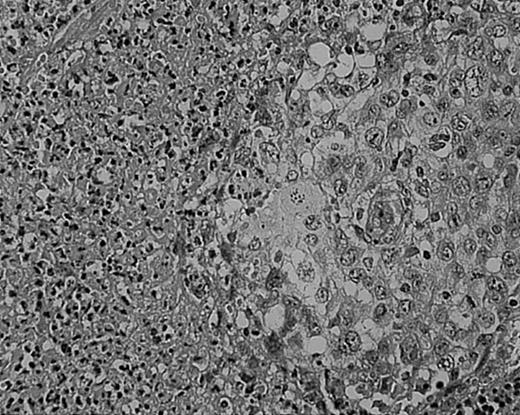

Cellular atypia (left-side confluent necrosis) in NS HD.

This example shows more than 25% of H/RS cells presenting with bizarre and anaplastic appearances. Stained with H&E. Original magnification, × 400.